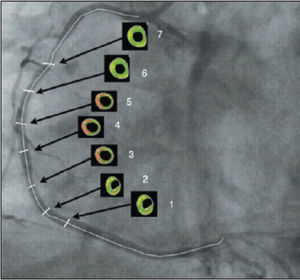

After locating the cross-section with the highest rate of arterial remodelling, termed the cross-section of interest (cross-section 4) and the performance of quantitative measures of intravascular ultrasound and evaluation with Virtual Histology®, the evaluation of six more cross-sections was performed with five frames of difference; three proximal to and three distal to crosssection 4 (Figure 1).

After quantitatively analyzing the percentage of necrotic core in the atheromatous plaque and arranging the results in charts according to the analyzed crosssection, the representation of the amount of necrotic core along the studied segment is visualized. Cross-section 1 represents the most distal cross-section of the vessel, while cross-section 7 is the most proximal. Cross-section 4, or the cross-section of interest, and cross-sections 2, 3, 5, and 6 complement the representation of the chart for the quantitative understanding of the necrotic core in the segment of the coronary artery studied.

The analysis of the variation in the percentage of necrotic core between the seven cross-sections of the coronary artery, using analysis of variance for repeated measures, showed higher amounts of necrotic core in the cross-section of interest, which has the highest rate of vascular remodelling (Figure 3).